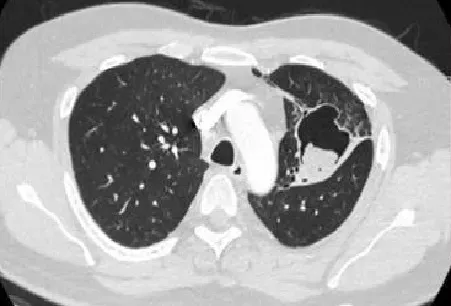

Gần đây, bệnh nhân thường xuyên ho ra máu nhiều nên đến khám tại một bệnh viện trên địa bàn TP. Hồ Chí Minh. Tại đây, bệnh nhân được chẩn đoán u nấm phổi bên trái trên nền lao phổi cũ.

Dựa trên các kết quả lâm sàng tại các cơ sở y tế nơi bệnh nhân đến khám trước đó, các bác sĩ nhận định đây là trường hợp u nấm phổi ở thùy trên phổi trái, lựa chọn cắt thùy phổi là cần thiết để điều trị triệt để ho ra máu.

Bệnh nhân được tiến hành phẫu thuật cắt bỏ thùy trên phổi trái kèm theo hang nấm. Trong quá trình mổ, ekip các bác sĩ nhận thấy thùy trên phổi trái có u cạnh rốn phổi dính vào thùy dưới khá phức tạp nên đã tiến hành gỡ dính u với thành ngực và động mạch chủ. Ca phẫu thuật diễn ra thành công sau 3 giờ.